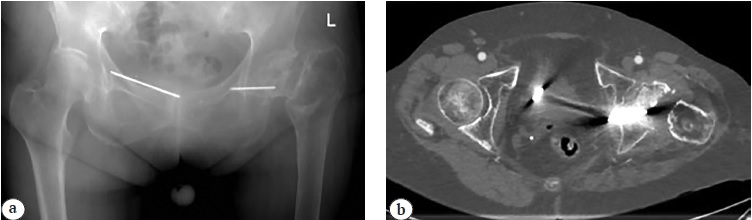

Fig. 2. C-arm fluoroscopic images: a — wire in the bladder area; b — results of cystography; c — forceps in the bladder; d — endoscopic removal of the wire; e — control image after wire removal from the bladder

With the patient in supine position under endotracheal anesthesia, the operative field was treated with antiseptic solutions. No leakage of the contrast agent from the bladder cavity was registered (Fig. 2 a, b). Cystoscopy revealed migrated K-wire in the bladder cavity. The foreign body was removed using endoscopic forceps (Fig. 2 c, d). Control contrast-enhanced fluorography showed no contrast leakage (Fig. 2 e). Control X-ray was performed, in which a remainder of the wire was visible in the hip joint area (Fig. 3 a, b).